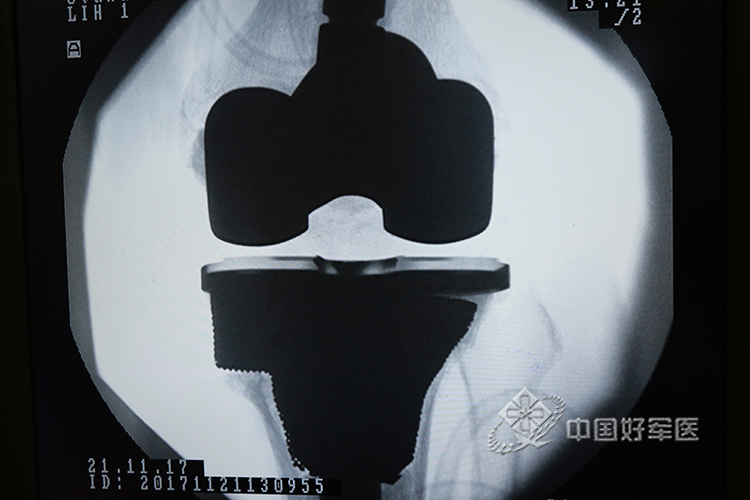

术后x光片 (1)

术后x光片 (2)

术后x光片 (3)

术后x光片 (4)